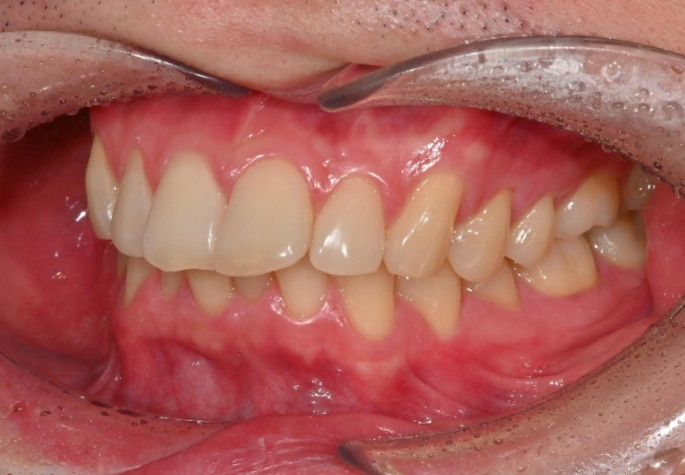

윗니 뻗침으로 인해 위 아래 간격이 크면 아랫입술이 그 사이로 숨습니다.

그래서 초진 아랫입술이 얇아보이는 거죠.

25.02~25.12

교정 후 위아래 간격이 줄면서 아랫입술이 제 모습을 드러냈습니다.

드라마틱한 돌출 해소는 포기한 간단한 인비절라인 라이트 교정이지만, 앞니 뻗침이라도 해결되니 미소가 한층 깔끔합니다.